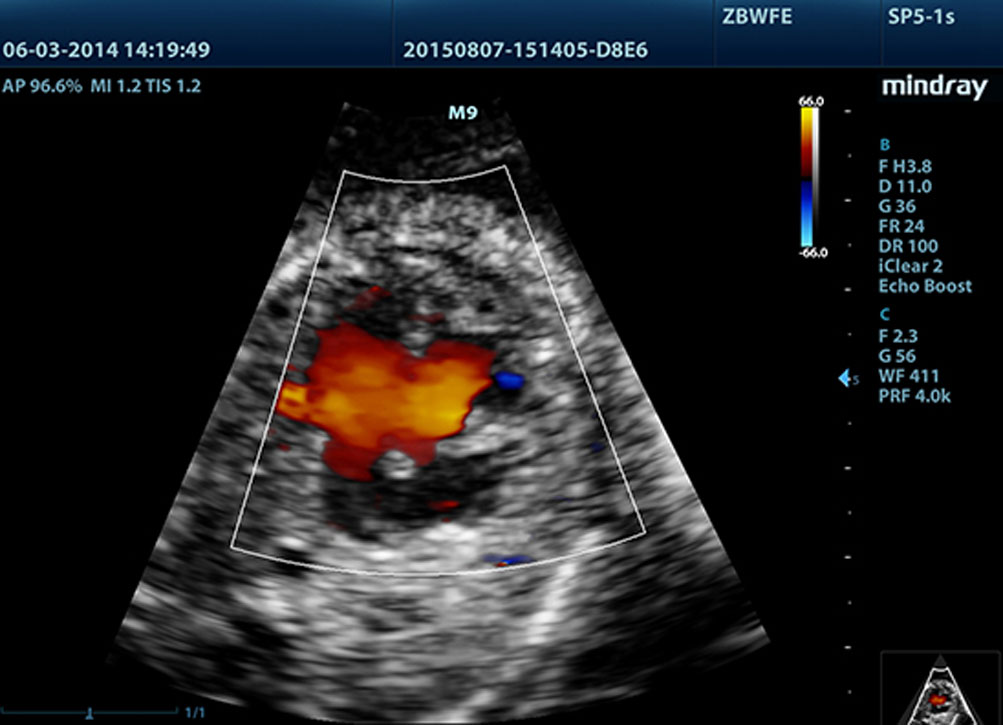

LVO mit Belastungsechokardiographie

Die au?ergew?hnlichen F?higkeiten des M9 erlauben eine LV-Eintr├╝bung unter Belastung und verbessern die Visualisierung der Endokardoberfl?che durch bessere Unterscheidbarkeit von Myokardgewebe und Blutpool. Die Belastungs-Echo-Funktion des M9 umfasst ein ganzes Paket pharmakologischer Belastung verschiedener Belastungs-Echo. Das Paket wird durch ein flexibles Berichtssystem?unterst├╝tzt, das gem?? Ihren individuellen Erfordernissen optimiert werden kann.